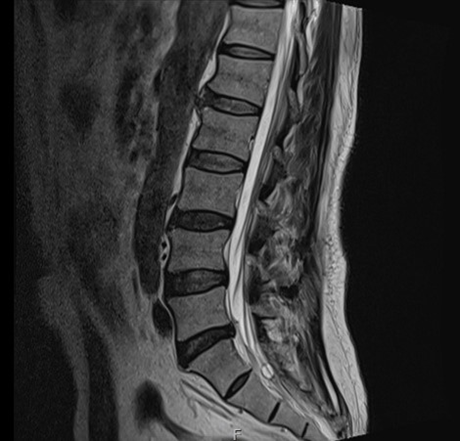

뇌 MRI, 척추 MRI 등 다양한 검사 결과,

약간의 디스크 증상이 있기는 하셨지만

그걸로 통증을 설명하기는 어려웠죠.

그림4.png 촬영 일시: 2025.05.23

<Fig 2. 척추 mri>